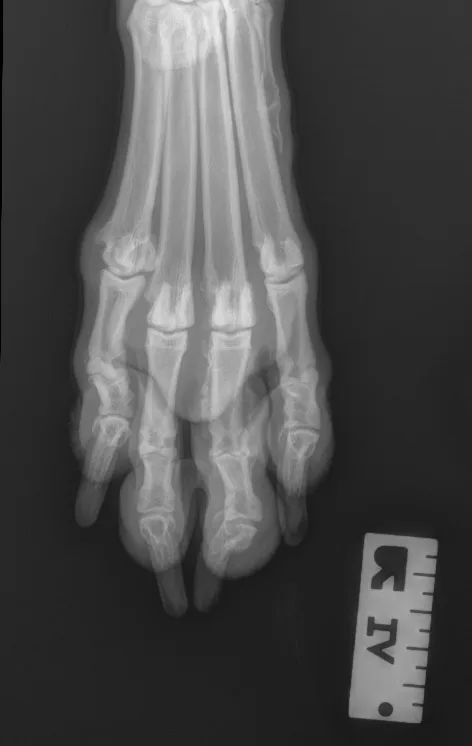

Step 1: Position the Patient

Place the patient in dorsal recumbency. Center the abdomen over a V-trough sponge positioner to keep the body straight; ensure the pelvis and caudal abdomen are outside of the trough. Make sure both pelvic limbs are completely extended and the unaffected limb is not in the imaging view.

Author Insight

To evaluate the entire bony structures, the digits may need to be separated manually (using either a wooden spoon to press down and spread the digits or using gauze without woven radiopaque detectors) and taped down.

Step 2: Position the Beam

Center the collimator beam over the tarsometatarsal joints to include the distal metatarsals and all digits (the tarsus can also be included).

All digits should be separated and clearly visible. The bony edges of the metacarpal bones should be parallel to each other (arrows), and all phalanges (P1 [A], P2 [B], P3 and nail [C]) should be included.